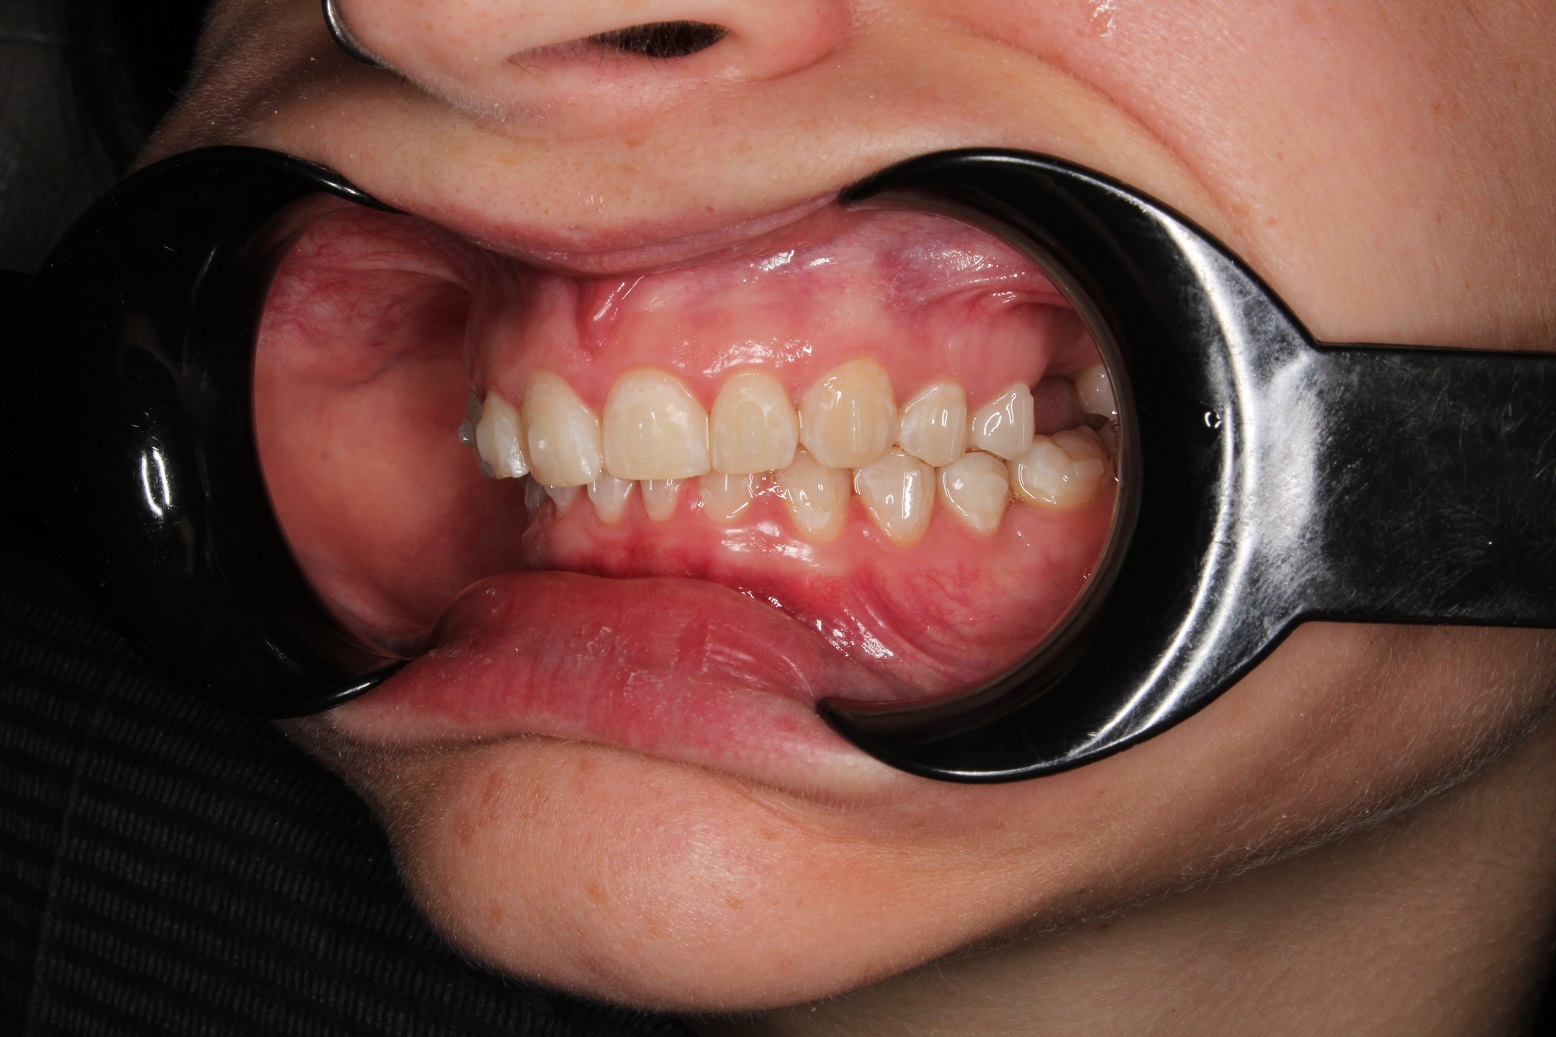

До и После: Лечение глубокого прикуса элайнерами

Лечение глубокого прикуса элайнерами. Начало лечения. Фиксация элайнеров